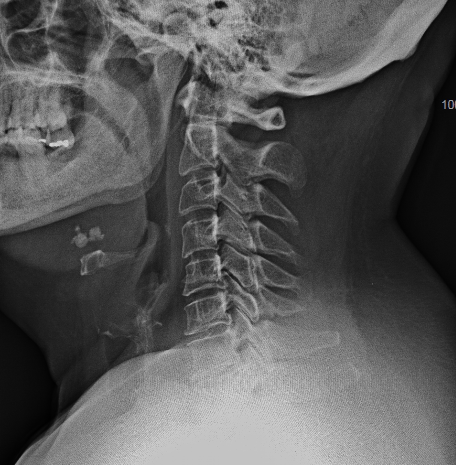

- a las peculiaridades anatómicas de la región: el mediastino anterior con los grandes vasos dificulta el acceso a la columna (inclusive a cirujanos torácicos y cirujanos vasculares). El abordaje clásico cervical puede requerir en los niveles más altos (Th1 y Th2) una esternotomía con osteotomía de clavícula y reconstrucción posterior. Generalmente, el cálculo del ángulo Thoracic Inlet Angle (TIA) puede predecir si será un abordaje más o menos dificultoso (para discos cervicales bajos o Th1-Th2 con TIA >60º). En estos casos, suelo informar al paciente la posibilidad de esternotomía (o completar con abordaje posterior la resección) y para el día de la intervención solicito la colaboración de un cirujano torácico. El abordaje posterior es mucho más sencillo, sin embargo plantea como principal dificultad técnica la imposibilidad de descomprimir el canal central en su sector anterior. Otro inconveniente a tener en cuenta en la elección de la vía posterior es la potencial secuela de cifosis secundaria a la resección de elementos de estabilidad posteriores (músculos, ligamentos, huesos), probable causa de dolor cervicotorácico mecánico.

En las imágenes de arriba se aprecian las dificultades anatómicas del abordaje anterior.

Obsérvese, en la imagen anterior, la incisión usada en relación con la prótesis. No fue necesario realizar ninguna esternotomía (aunque el cirujano torácico estaba avisado). Para mejorar la visión sí que se resecó parte del platillo inferoanterior de Th1.